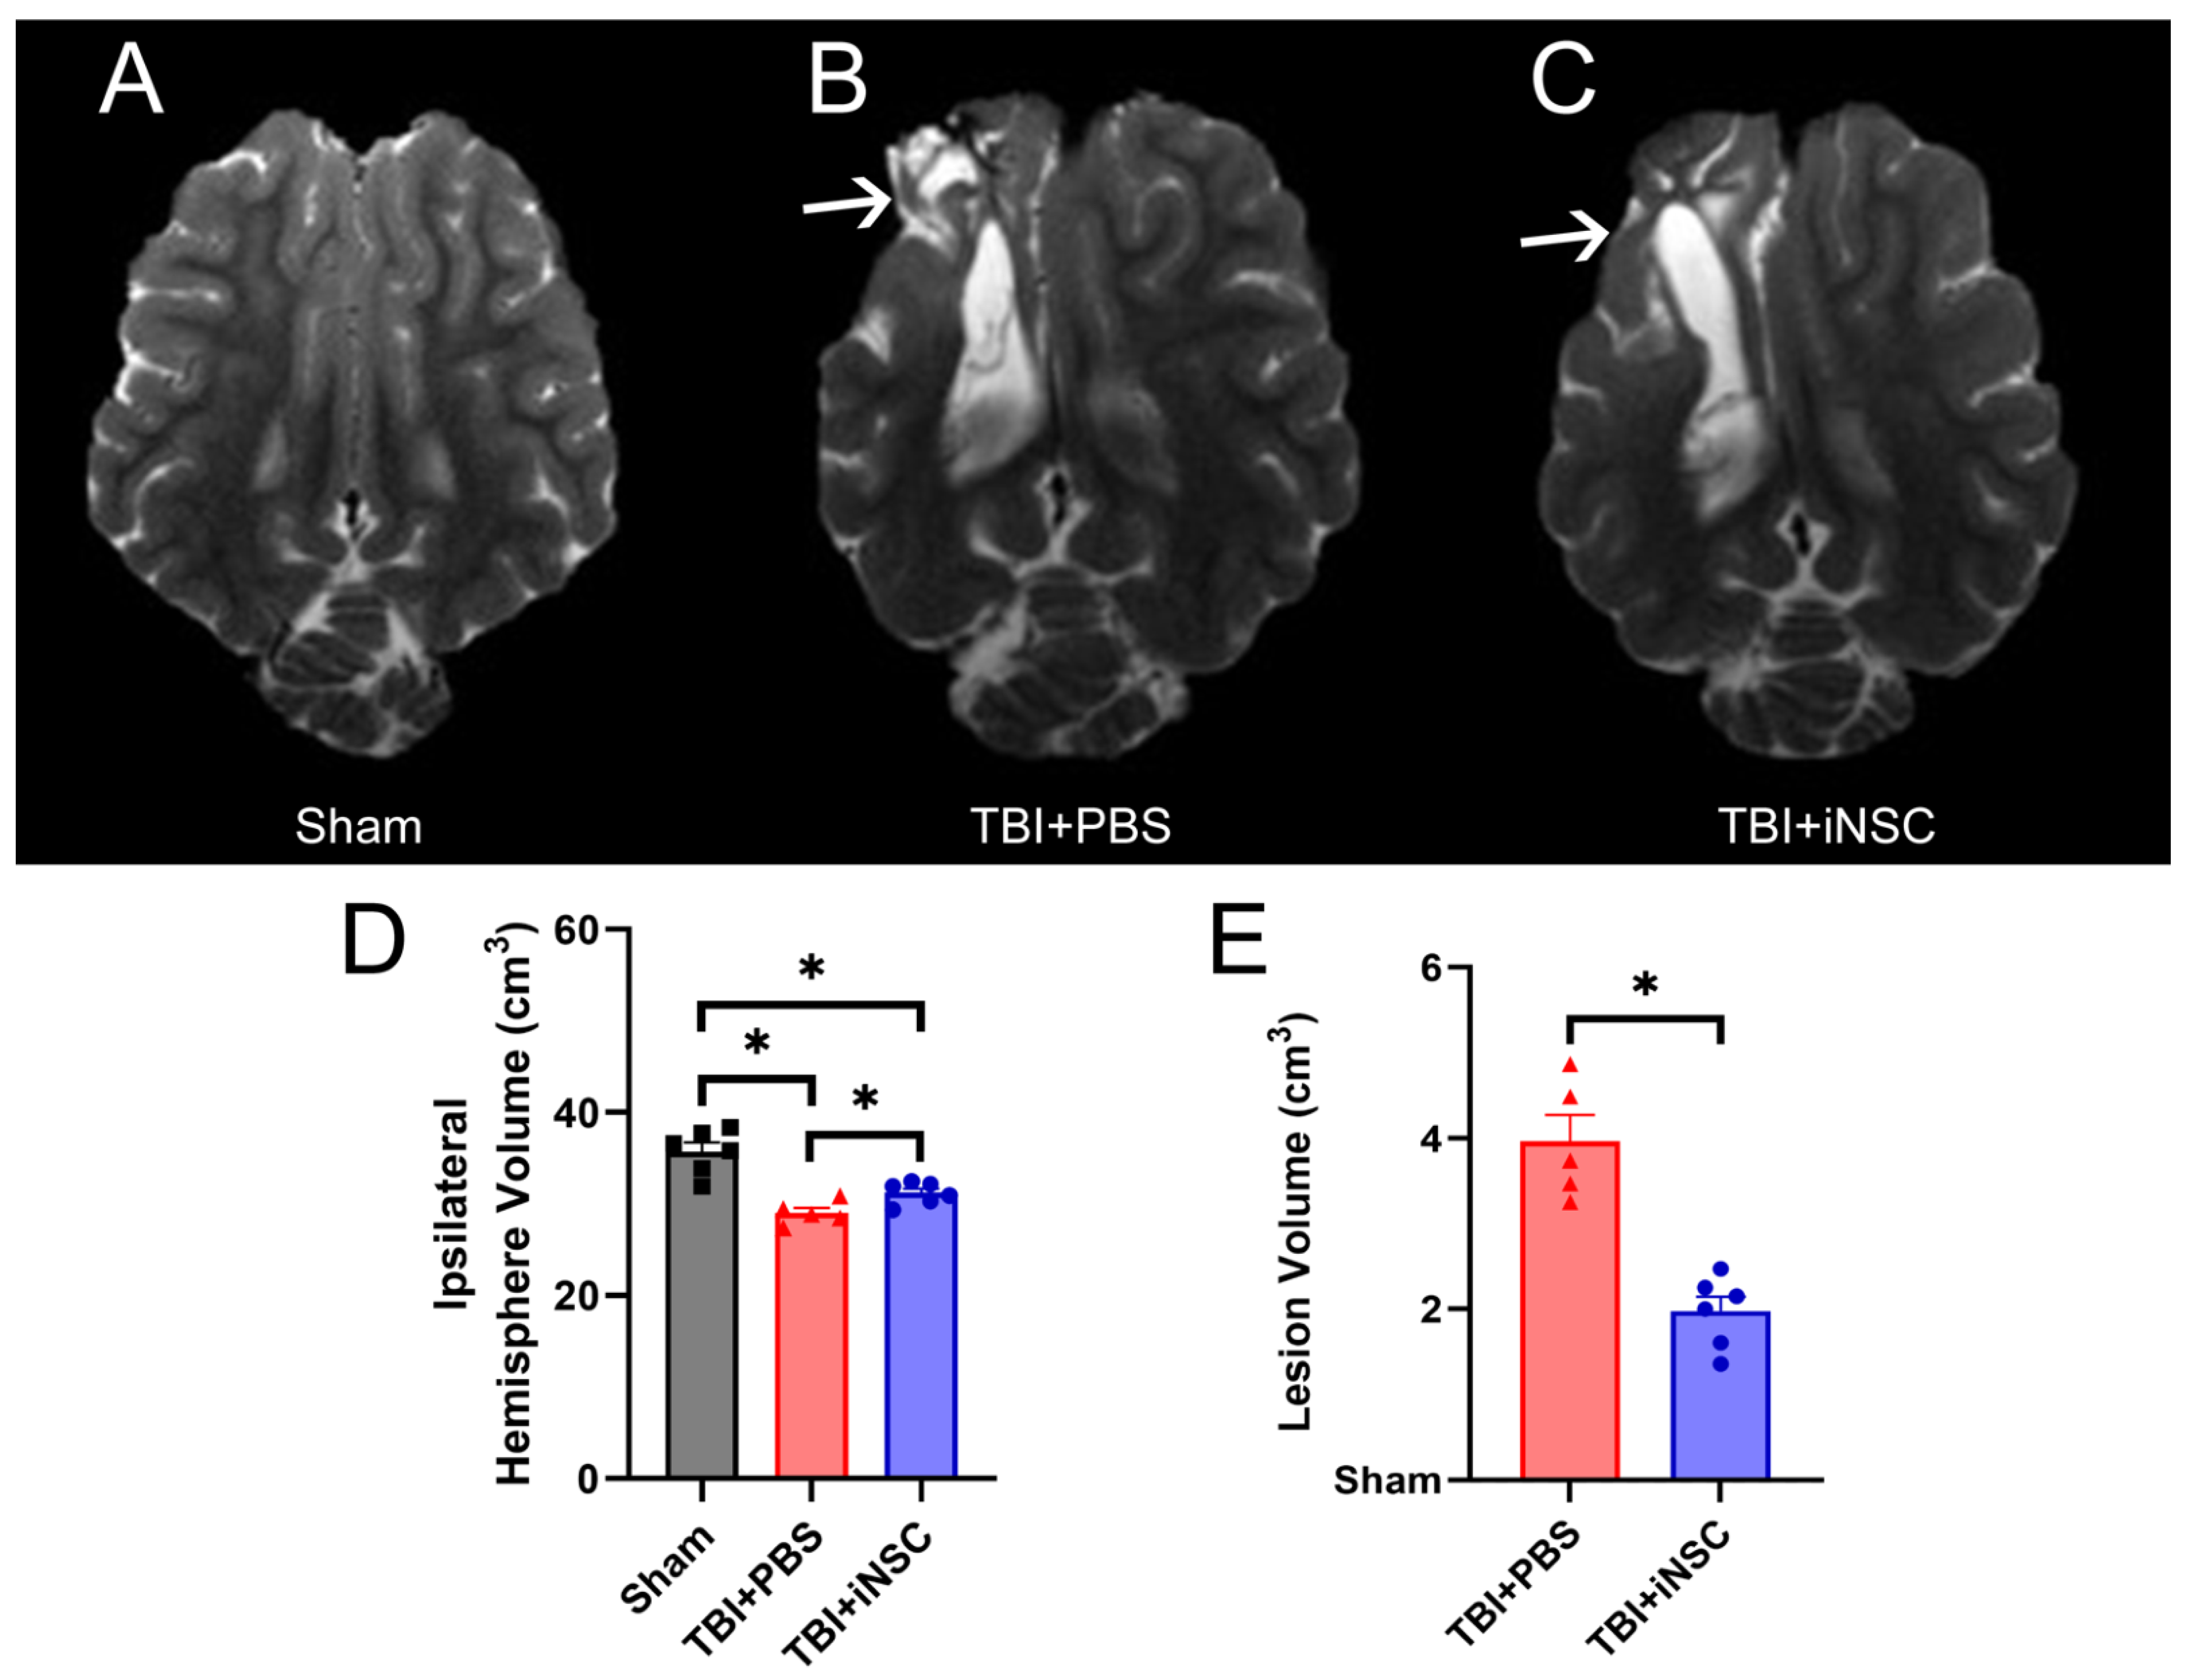

3.4. iNSC Transplantation Significantly Decreased Ipsilateral Atrophy, Lesion Volume, and Midline Shift While Preserving Cerebral Blood Flow